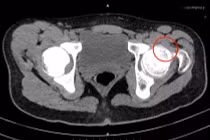

Mới đây, các bác sĩ Khoa Chấn thương Chỉnh hình, Bệnh viện Bãi Cháy đã phẫu thuật thay khớp háng cho bệnh nhân Vũ Kim H (40 tuổi, ở phường Móng Cái, tỉnh Quảng Ninh). Bệnh nhân có tiền sử hoại tử chỏm khớp háng hai bên, đã được phẫu thuật thay khớp háng trái cách đây 1 năm. Gần đây bệnh nhân xuất hiện đau và hạn chế vận động khớp háng phải.

Kết quả chụp xquang có hình ảnh đặc xương kèm tiêu xương không đều vùng chỏm xương đùi phải gây biến dạng xương đùi và hẹp không đều khe khớp háng phải. Các bác sĩ đã hội chẩn và đánh giá tình trạng hoại tử vô khuẩn chỏm xương đùi phải tiến triển và không còn khả năng bảo tồn. Người bệnh được chỉ định phẫu thuật thay toàn bộ khớp háng háng phải.